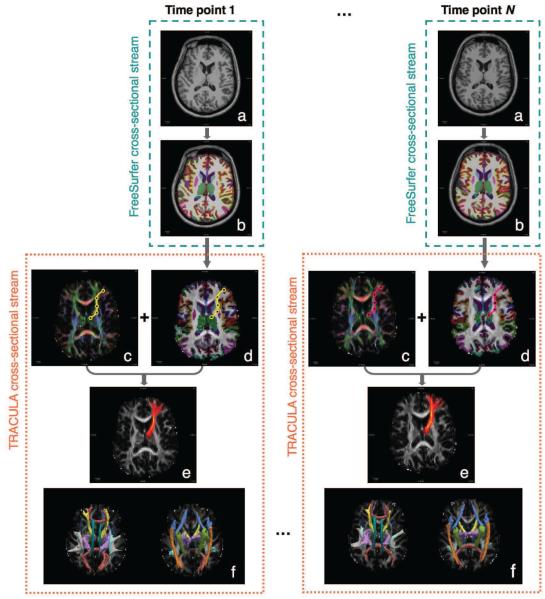

In the following, we will compare the longitudinal tractography described above to the conventional cross-sectional tractography approach, where the pathways are reconstructed independently from the data at each time point, as if it were a cross-sectional data point. The longitudinal and cross-sectional processing streams are illustrated, respectively, in Figures 1 and 2.

Figure 1. Cross-sectional tractography.

In the cross-sectional analysis approach, we process the data from each time point independently. The subject’s T1-weighted image from each time point (a) is processed with FreeSurfer to yield a cortical parcellation and subcortical segmentation (b). The path of interest is represented as a spline in each time point’s native DW image space independently (yellow curve for time point 1, magenta curve for time point N here). For each time point, the diffusion orientations (c) are estimated from the DW images and used to compute the likelihood of the path, whereas the cortical parcellation and subcortical segmentation labels are aligned with the DW images (d) and used to compute the prior probability of the path. The control points of the path are perturbed repeatedly and all the accepted paths are accumulated to estimate the posterior distribution of the path at each time point (e). This is repeated for each of the 18 pathways. Their posterior distributions are shown in (f) as isosurfaces thresholded at 20% of the maximum probability for each pathway.